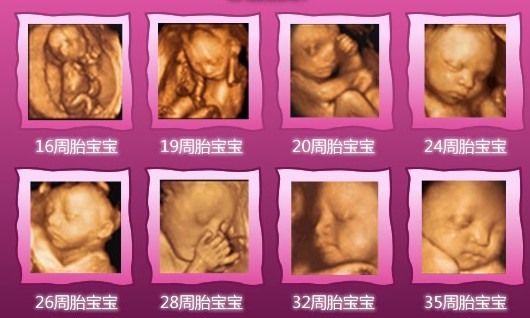

杭州玛莉亚妇产医院产科专家表示:孕妇在不同的怀孕阶段做四维彩超,照出来的效果会有所不同,为了能够得到更加清楚的检查结果,建议准妈妈们怀孕23―27周内做胎儿四维彩超,此时胎儿发育基本成型,羊水量适中,较适合做胎儿畸形筛查.

在佳的时间内做四维彩超不仅能够准确的检查胎儿有无畸形,还能让准爸妈们提前一睹宝宝可爱的模样,见证0岁宝宝神奇的发育过程,在检查过程中还能为宝宝拍摄宫内写真和动态录像,为枯燥的孕期检查增添了乐趣.